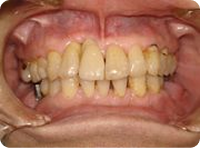

治療前

前歯が歯周病のためグラグラで今にも抜けてしまいそうな状態です。

治療後

抜歯と同時にインプラントを植立し、3ヵ月後にセラミックの冠を装着しました。